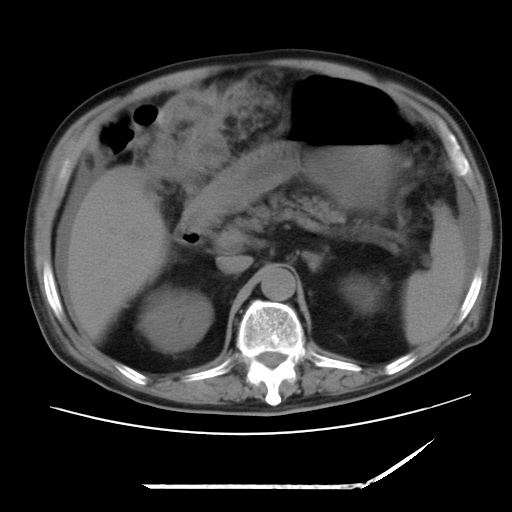

以下是引用zxl51642在2009-8-12 18:55:00的发言:[br]1、肠系膜脂肪浑浊,密度增高,腹水,支持腹膜炎诊断;2、右肾盂及输尿管中段结石,左输尿管起始段结石;3、胆囊切除术后改变?4、双侧胸膜腔少量积液;5、胰腺体积不大,勾勒清楚,肾前筋膜无增厚,不支持胰腺炎,请结合血尿淀粉酶及临床。